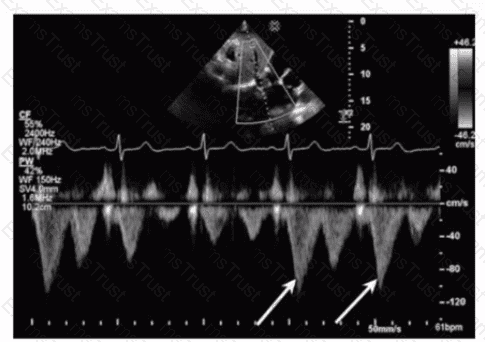

Which flow component is indicated by the arrows on this image?